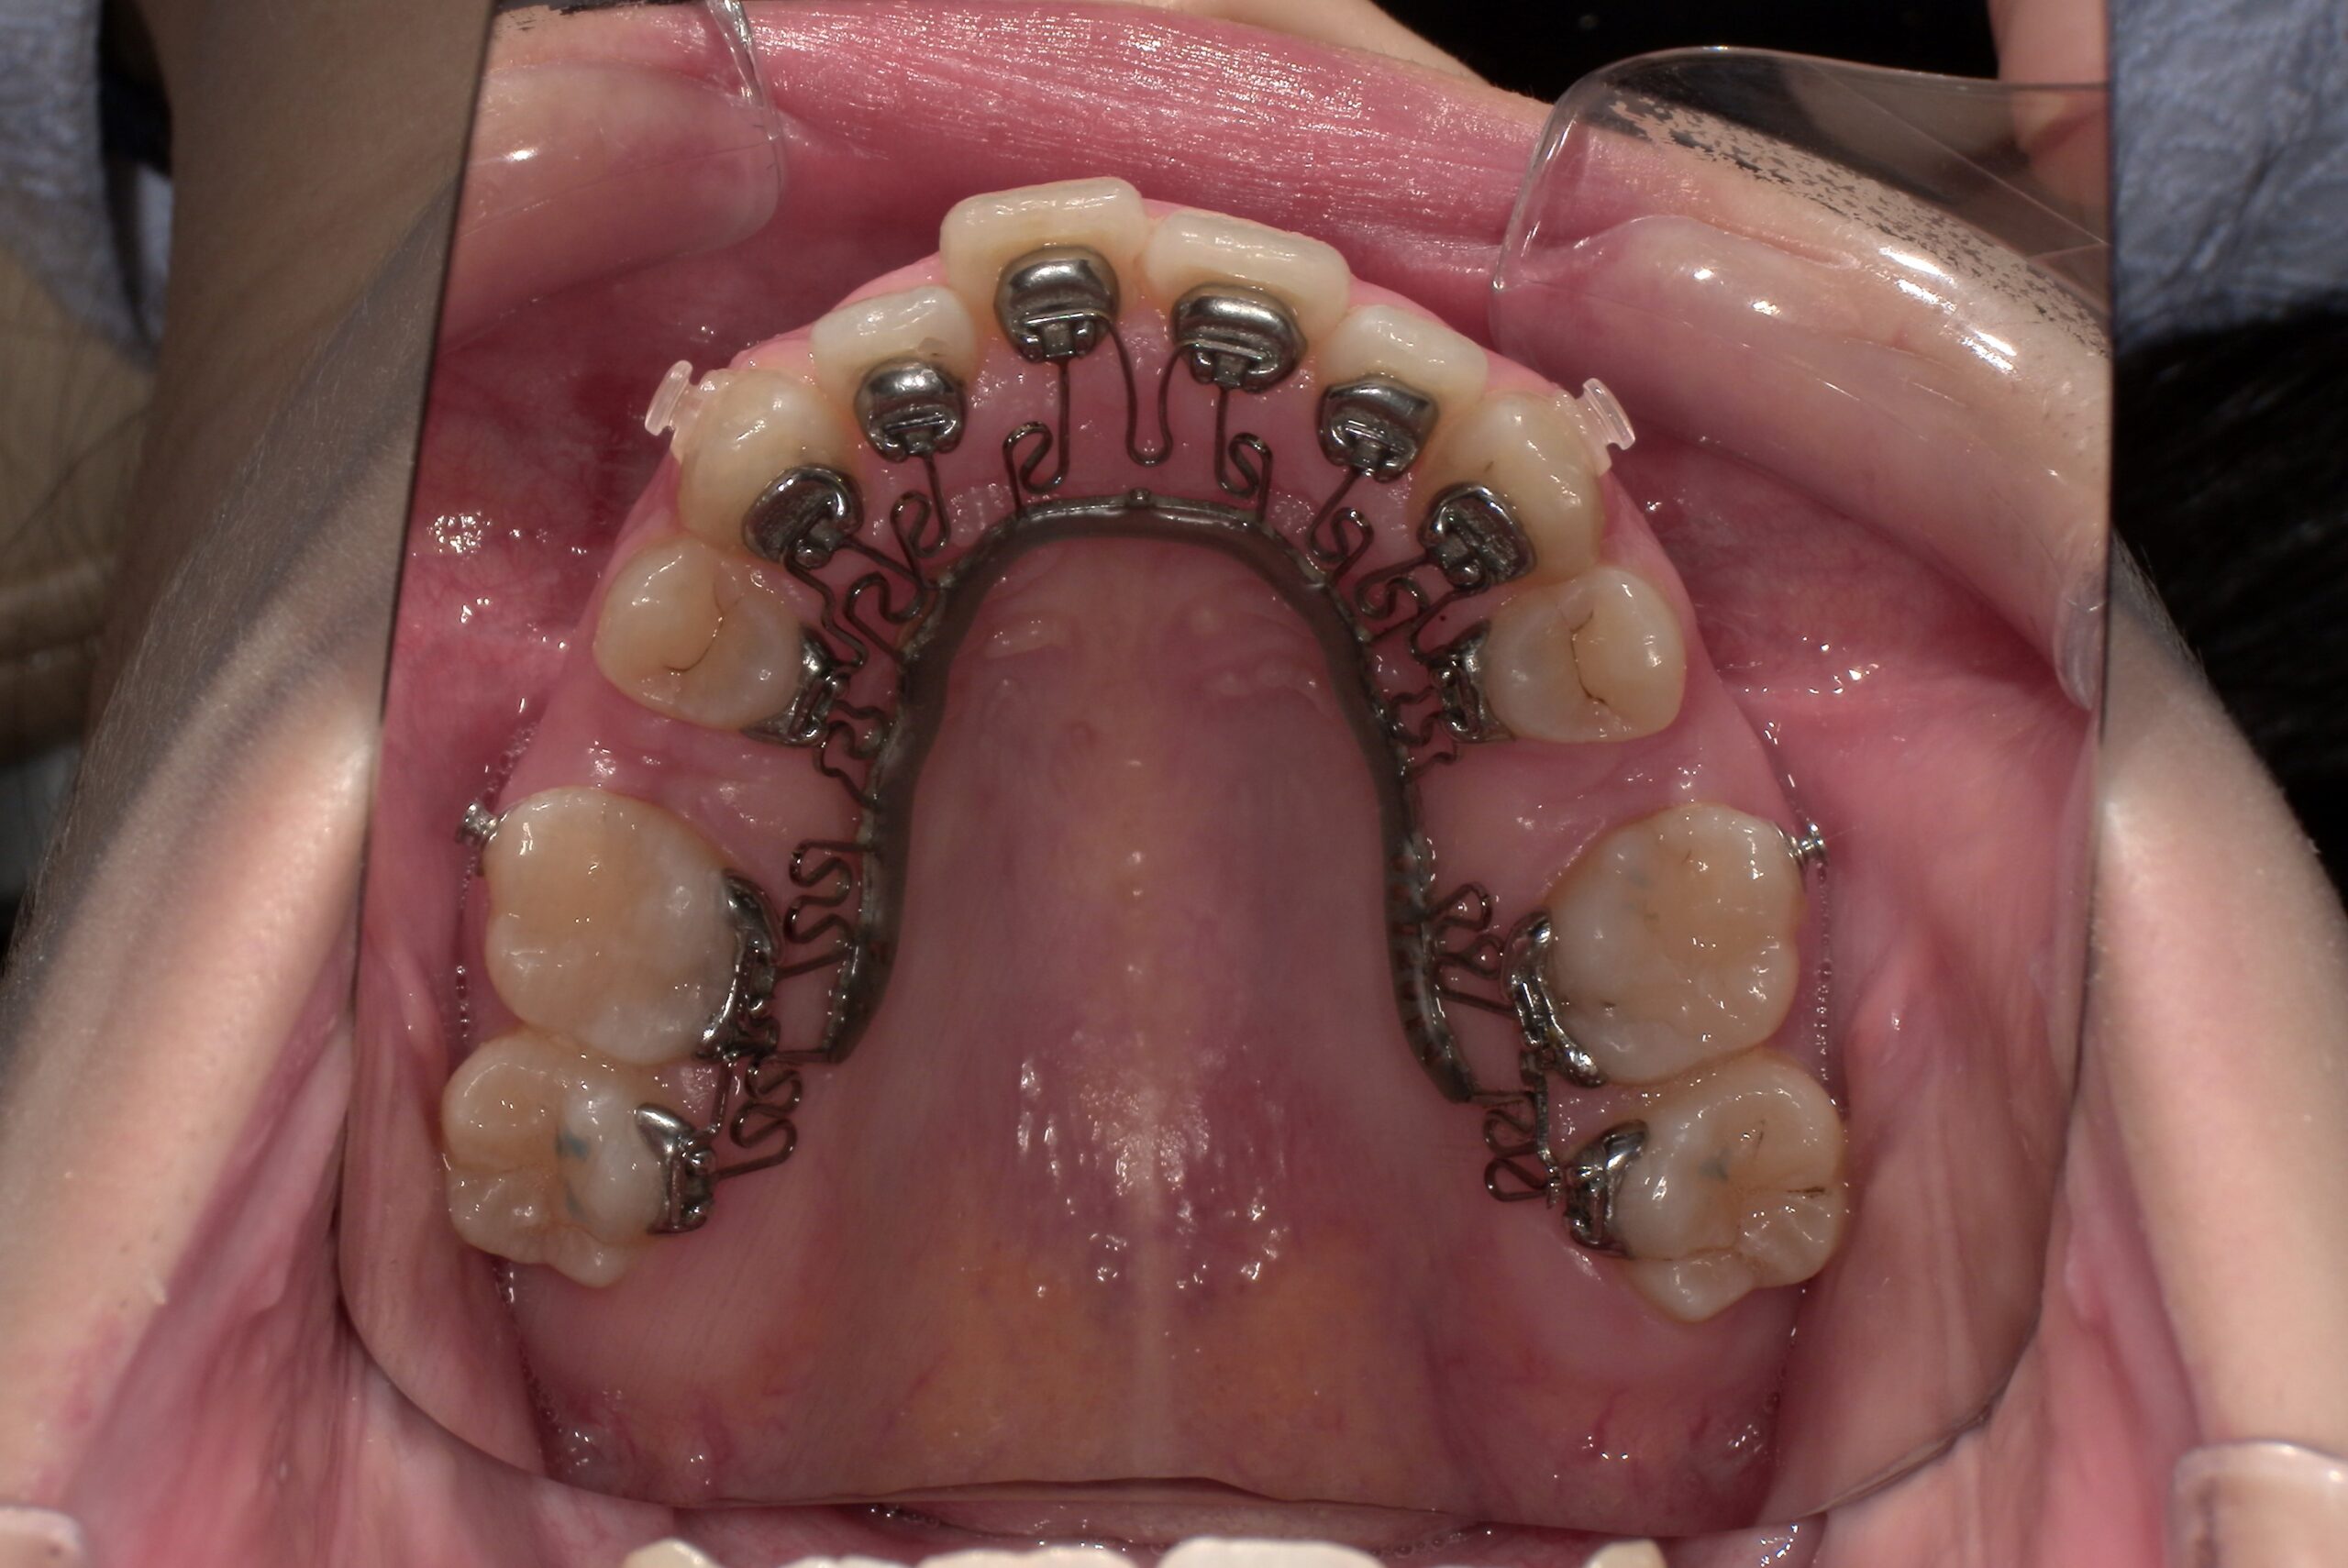

📸治療経過写真

当院で裏側矯正治療しているスタッフの経過写真をご参考にしてください。

上下左右小臼歯を1本ずつ計4本抜歯して現在も治療中です。「歯を抜いた隙間が閉じた量」、「前歯の移動量」、「正面から見た前歯の位置」に注目して見てもらえると、歯の移動の早さが目に見えて分かるかと思います。

初回装着時

上顎

(青い材料は下の歯が上の装置にぶつからないよう、咬み合わせを一時的に上げる材料です)